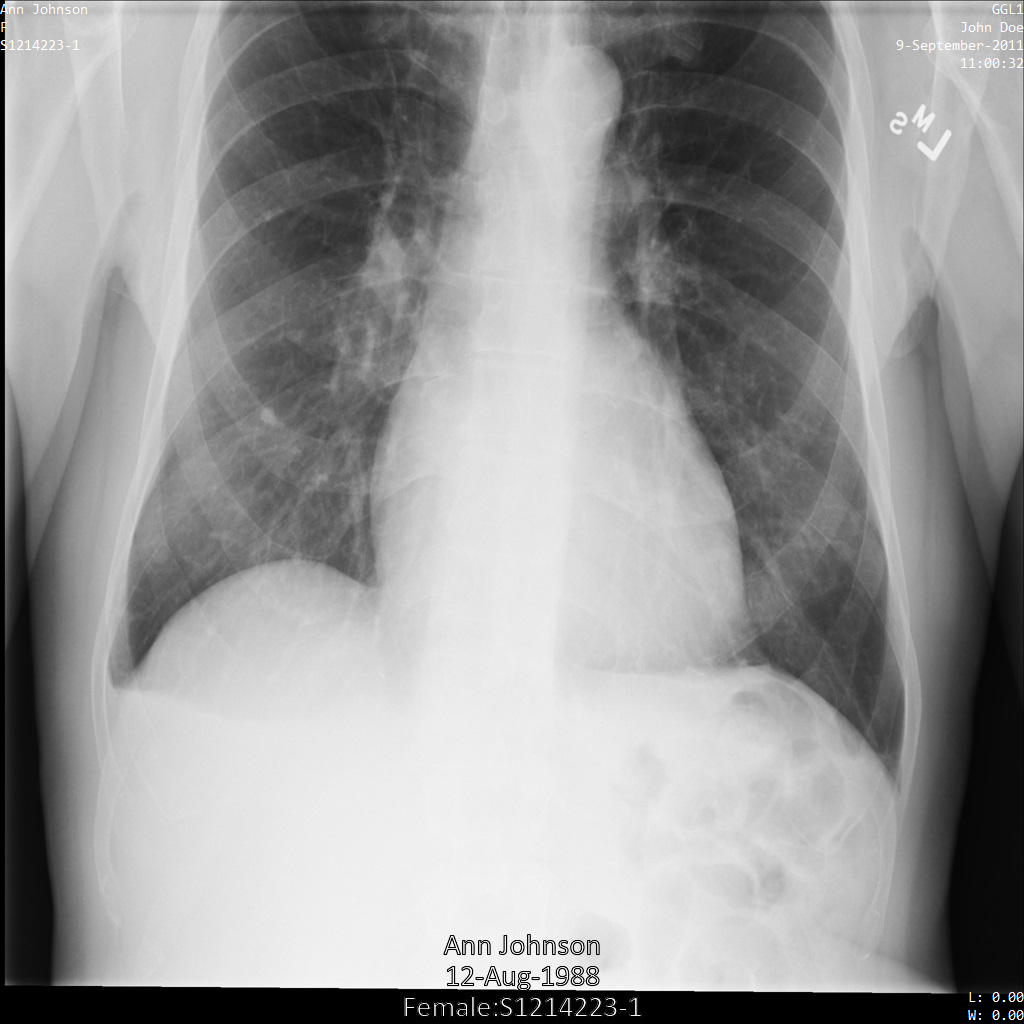

以下各節提供範例,說明如何使用各種方法去識別 DICOM 資料。每個樣本都會提供去識別化圖片的輸出內容。每個範例都會使用下列原始圖片做為輸入內容:

您可以比較各項去識別化作業的輸出圖片與原始圖片,瞭解作業效果。

將圖片提交給 Cloud Healthcare API 後,圖片會如下所示。雖然圖片頂端角落顯示的中繼資料已遭塗銷,但圖片底部的內建受保護健康資訊 (PHI) 仍存在。如要一併移除內建文字,請參閱「從圖片中遮蓋內建文字」。